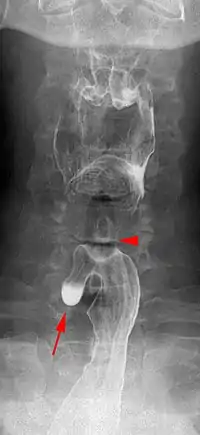

| Killian–Jamieson diverticulum. Arrowhead points at the closed upper esophageal sphincter, arrow points at the diverticulum partly filled with contrast medium. | |

A Killian–Jamieson diverticulum is an outpouching of the esophagus just below the upper esophageal sphincter.[1]

The physicians that first discovered the diverticulum were Gustav Killian and James Jamieson. Diverticula are seldom larger than 1.5 cm, and are less frequent than the similar Zenker's diverticula. As opposed to a Zenker's, which is typically a posterior and inferior outpouching from the esophagus, a Killian–Jamieson diverticulum is typically an anterolateral outpouching at the level of the C5-C6 vertebral bodies, due to a congenital weakness in the cervical esophagus just below the cricopharyngeal muscle. It is usually smaller in size than a Zenker's diverticulum, and typically asymptomatic.[2] Although congenital, it is more commonly seen in elderly patients.[3]